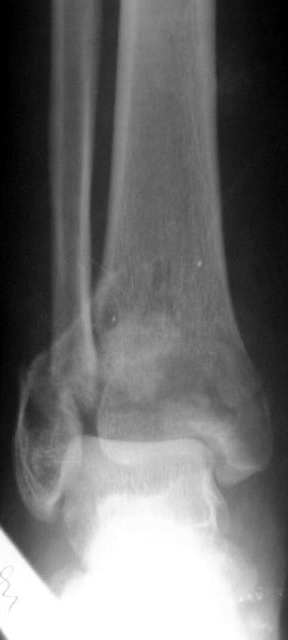

Перелом 43С

Поступил больной 57 лет 14.06.04 в наше отделение. Простой перелом малоберцовой кости Взрывной перелом дистальных отделов болыпеберцовой кости,

Вколоченный перелом дистальных отделов большеберцовой кости. Проводим репозицию с помощью скелетного вытяжения, перед операцией. Думаем как собрать б/б кость? Какой доступ использовать? Может сразу первичный артродез? Как то в форуме говорилось о доступе через м/б кость для артродеза. Возможно ли его использовать в данном случае? Если кто-то его использует, может поделится информацией, как правильно его делать? Сергей Зырянов НСО г Куйбышев.ЦРБ